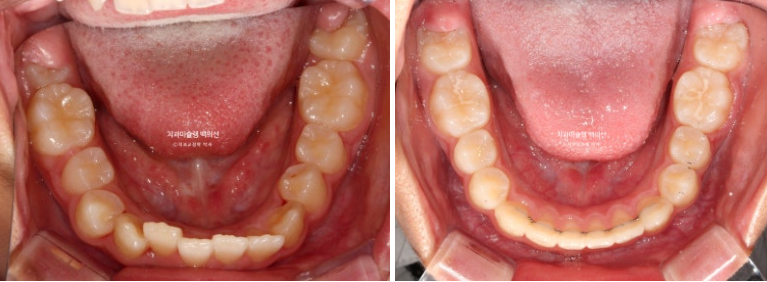

공간부족으로 인한 덧니가 심해 반대교합이 있습니다.

24.02

중심선은 개선되었으나 약간의 불일치가 남아있으며 반대교합과 덧니는 모두 개선되었습니다.

24.09

그 사이 하나 남아있던 유치가 빠지고 완전한 영구치열에 접어들었습니다.

교합과 아래배열은 완벽하게 유지되고 있습니다.